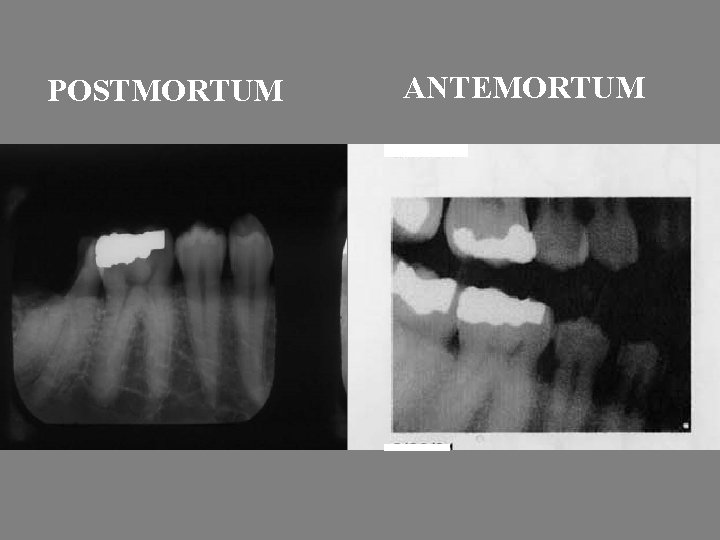

Identification of Human Remains • Post-Mortem resection of non-viewable remains • Radiography of intact or fragmented jaws • Charting of post-mortem examination • Obtaining and charting of ante-mortem records • Comparison of data

POSTMORTUM ANTEMORTUM

• A match?

Details for Comparison 1. Fillings 2. Extractions 3. Surface structure/root configuration 4. Adjacent teeth 5. Twisted/tilted teeth